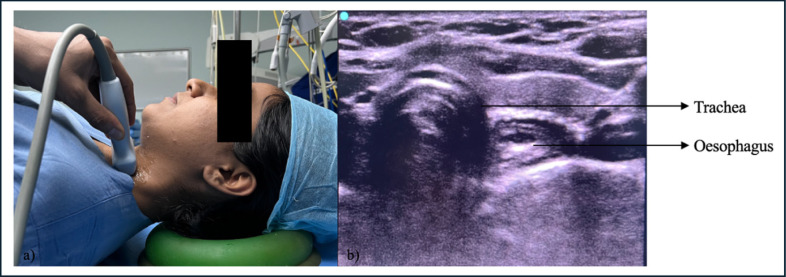

目的:气管插管成功是先进气道管理的关键步骤。气管插管成功的金标准是潮末二氧化碳(etCO2)监测,尽管最近的研究表明超声波也可以使用。在本研究中,我们通过比较超声和etCO2监测,探讨了气管插管成功的时间敏感性早期识别。方法:本研究纳入了104例在全麻下需要气管插管的择期手术患者。将取下面罩到超声显示气管颤振的时间与气管插管后连续6次超声波形的出现时间进行比较。结果:超声识别气管插管成功的时间为(21.63±7.38)秒,比超声检查(40.62±7.93)秒更快。结论:eCO2需要6次连续波形时间才能确认插管成功,且存在假阳性率。在不需要正压通气的低肺血流量患者中,如在心肺复苏期间,在创伤等高风险紧急插管中,或在可以实时确认插管的困难气道中,用超声补充金标准etCO2更快、更可靠。超声是一个可靠的和更快的工具,早期识别成功的气管插管比末潮二氧化碳。

Methods: The study included 104 patients who were posted for elective surgery under general anaesthesia requiring endotracheal intubation. The time from removal of the face mask to ultrasound visualization of flutter in the trachea was compared with that of the appearance of six consecutive capnography waveforms following endotracheal intubation.